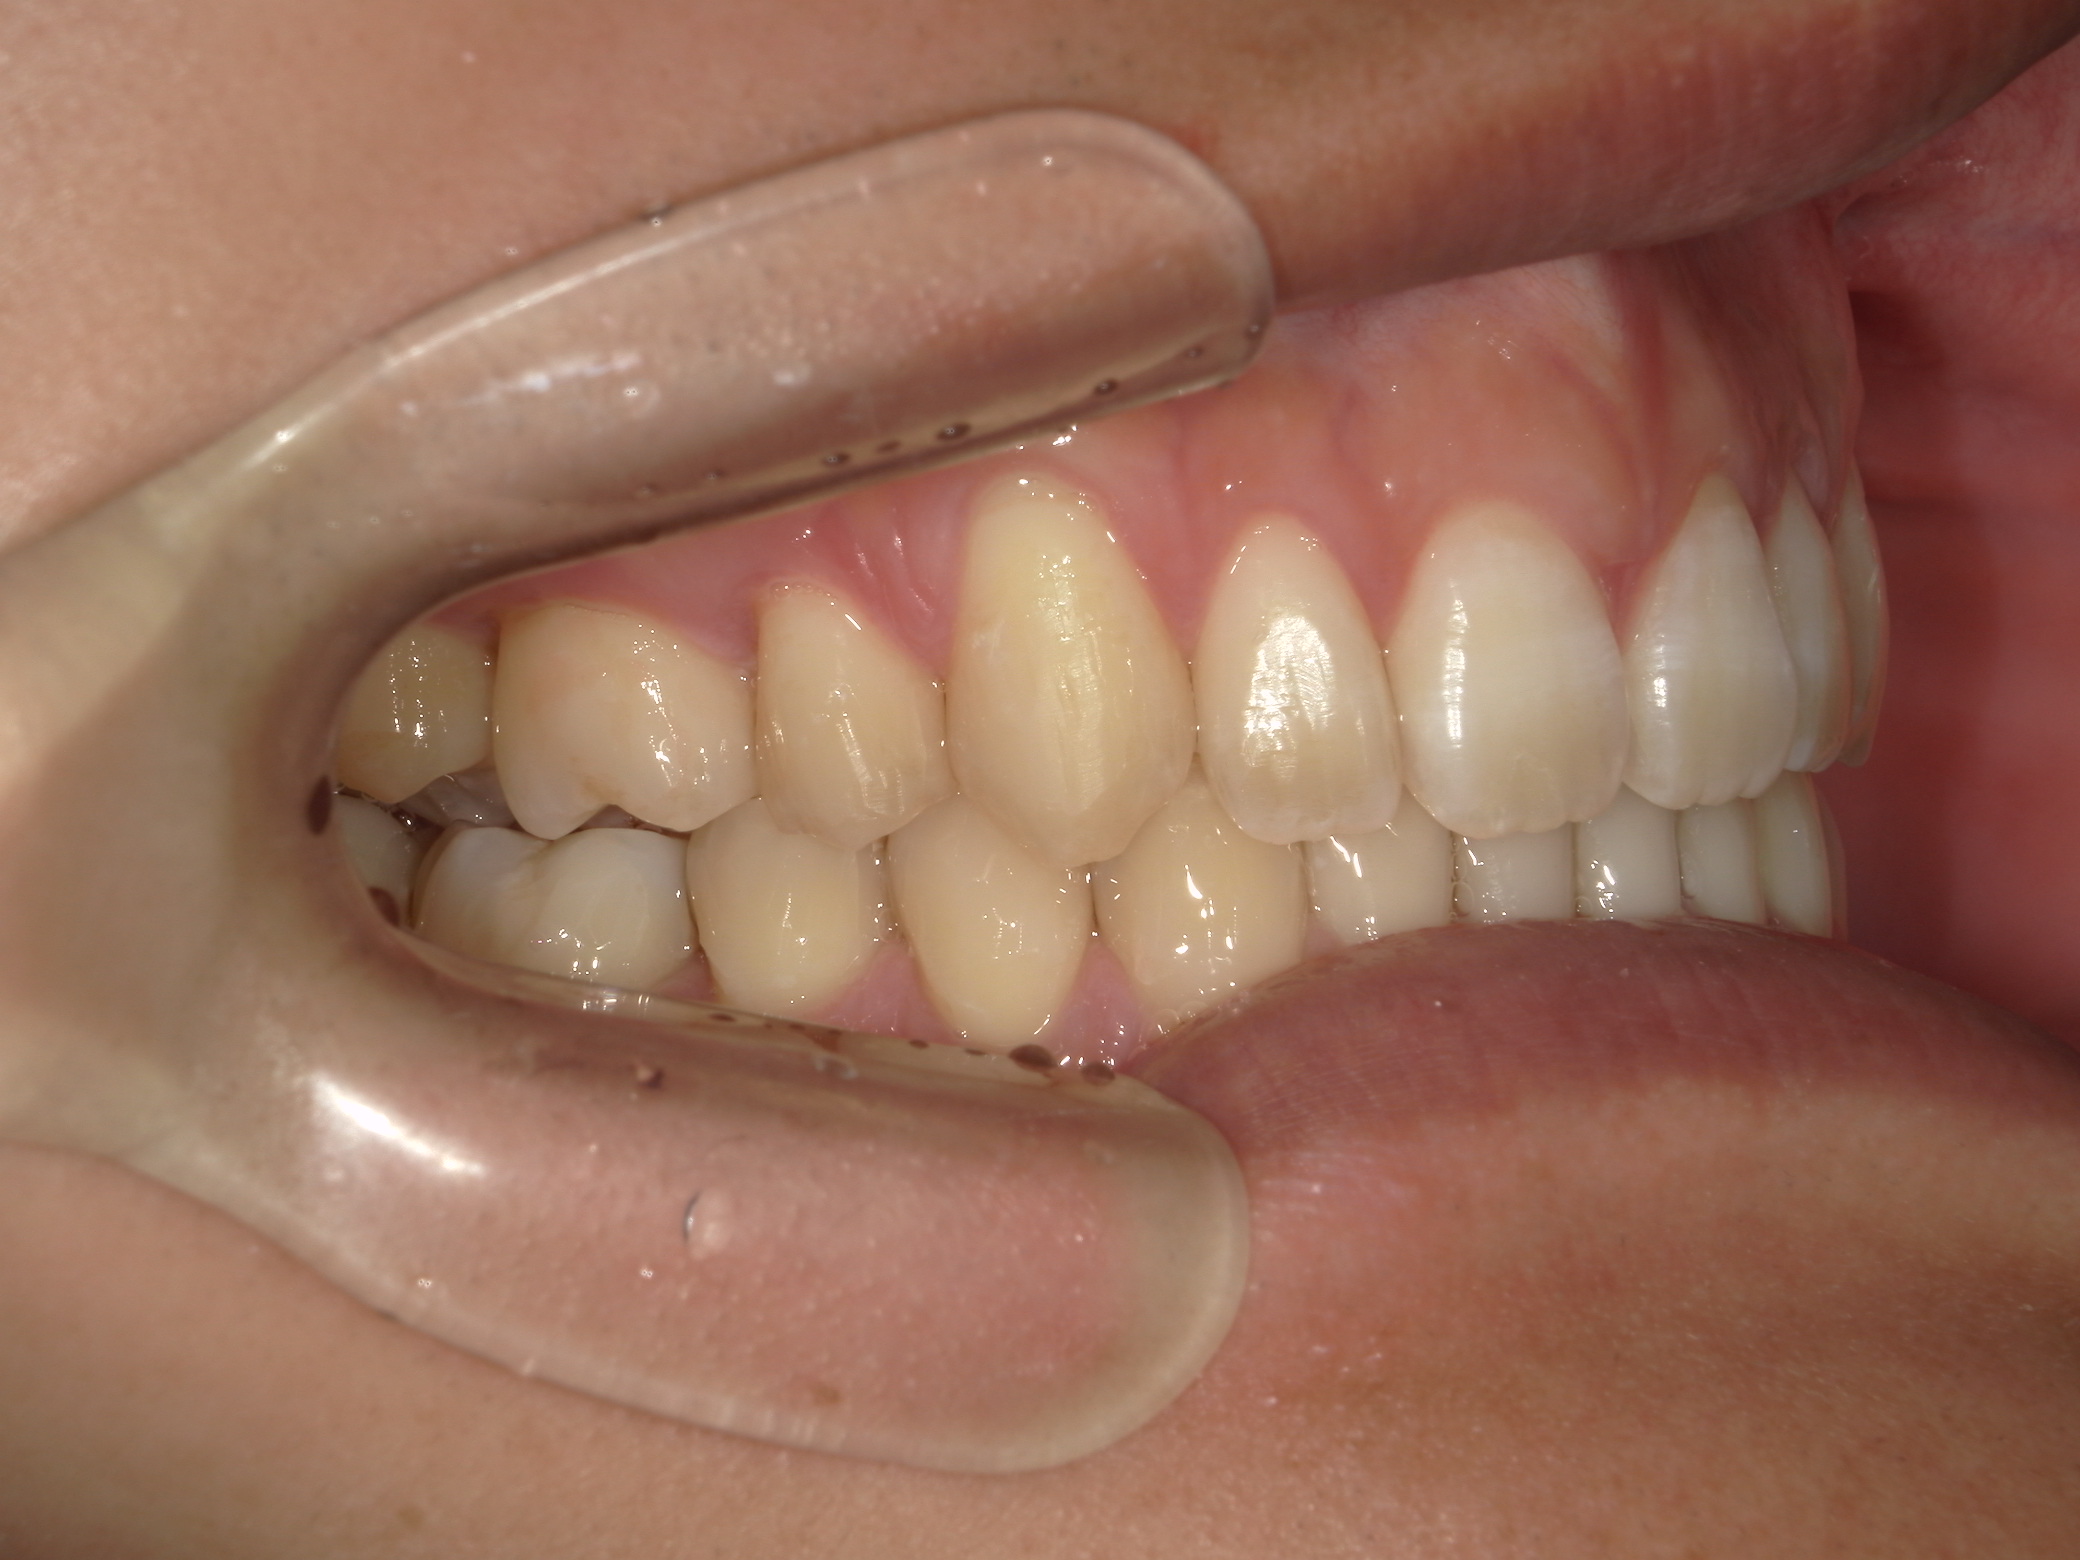

インビザライン矯正 症例(24)

主訴: 前歯の隙間が気になる。

左右上 第一小臼歯(2本)を抜歯。

スライスカットを併用。

カテゴリー : 隙間がある(空隙歯列)